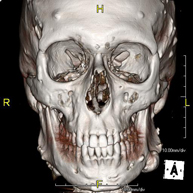

- TC Macizo facial  Prueba radiológica que consiste en obtener imágenes del macizo facial (cara) de alta definición anatómica mediante el empleo de un equipo de TC (Tomografía Computarizada). Indicaciones: tumores, cirugía plástica. Prueba radiológica que consiste en obtener imágenes del macizo facial (cara) de alta definición anatómica mediante el empleo de un equipo de TC (Tomografía Computarizada). Indicaciones: tumores, cirugía plástica.